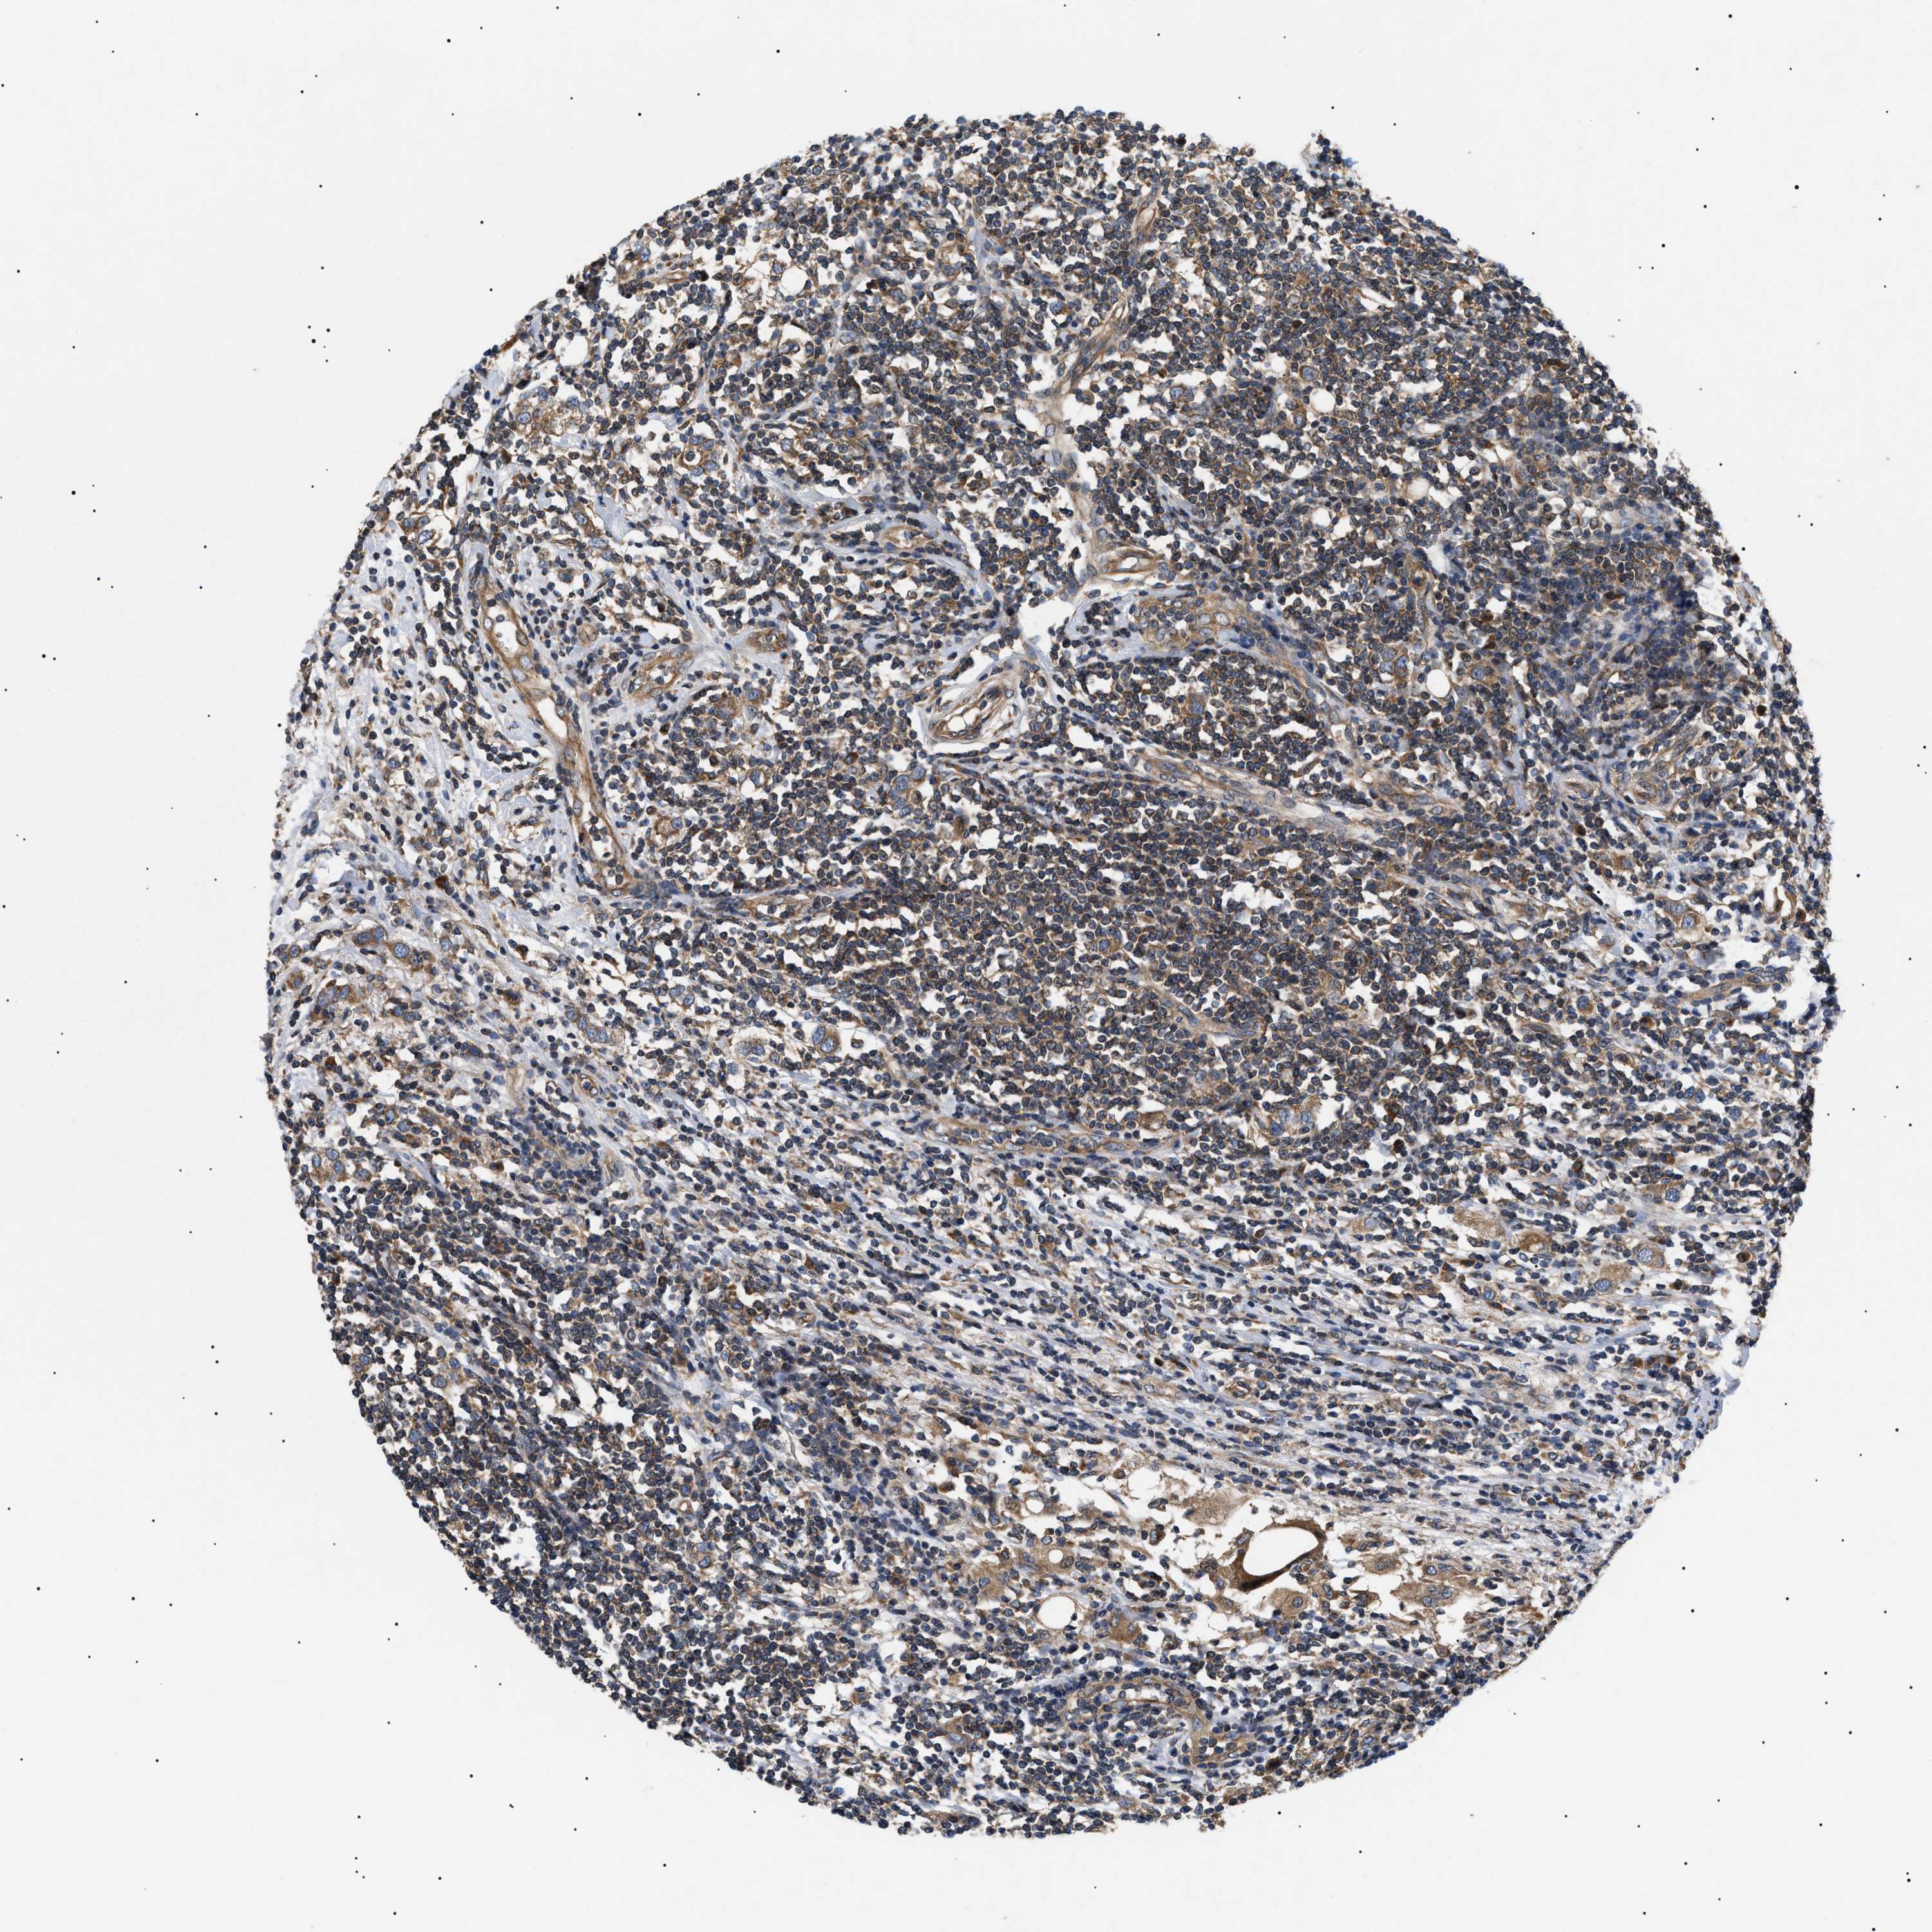

CANCER BREAST CANCER Show tissue menu

BRCA TCGA BRCA VALIDATION PROTEIN EXPRESSION